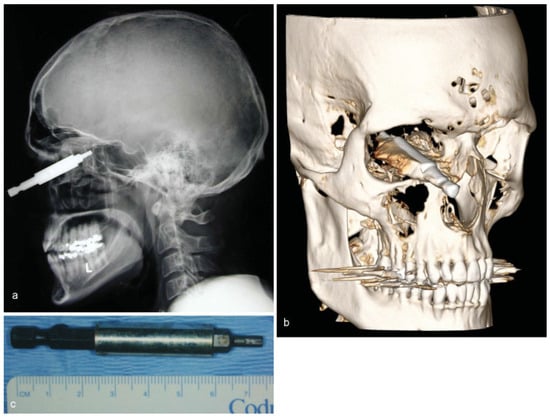

• Case 6: A 53-year-old patient suffered an impalement injury with a metallic drill, which had penetrated his neurocranium. The patient had tried to commit suicide, injuring himself in the thorax and head (Figure 6a,b). MDCT imaging displayed the position of the impacted drill, which had entered the skull at the front temporal cortex, and there was also an injury of the lung parenchyma (not shown). Following immediate thoracotomy to stabilize the patient, the drilling device was completely removed by osteoclastic trepanation performed by our colleagues in the neurosurgery department (Figure 6c). However, the patient subsequently died due to increased cerebral edema and severe damage to the brain parenchyma.

Figure 6. (a,b) Frontal and lateral skull radiographs showing a radiopaque foreign body penetrating intracranially. (c) Postoperative image of the metallic drill.